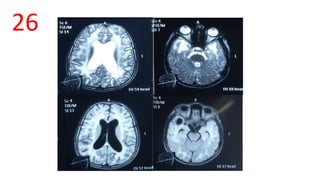

Van der Knaap disease

• T1- hypo, T2 and FLAIR- hyper

• bilateral subcortical cysts of CSF intensity affecting the anterior

temporal regions-T1 and FLAIR- - hypo, T2 hyper